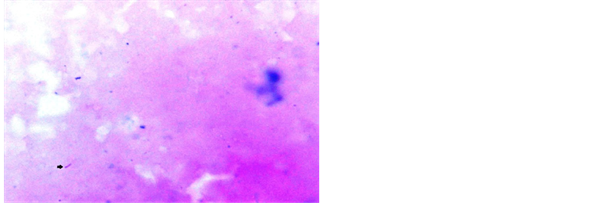

ZN stain was frequently used by various workers [11] [13] . Study conducted by Krishnaswammi and Job in 1972 on tissue sections shows 91 (71.1%) positive for AFB after ZN staining among 128 lymph nodes having tuberculous lymphadenitis [14] . Study conducted by Greenwood and Fox in 1973 shows 33 (47.1%) positive for AFB on ZN staining technique out of 70 tuberculosis histology cases [15] . Study conducted by Eshete and others in 2011 shows 37 (61.7%) positive for AFB after ZN staining technique in 60 lymph nodes with tuberculous histology [16] . Study conducted by Rasool et al., in 2017 shows 52.58% positive for AFB after routine ZN stain [17] . Our study has revealed 54% positive for AFB after ZN stain in tissue biopsy and their touch preparations shows 48% positive for AFB after ZN staining (Figures 4-6).

Figure 4. Photomicrograph of lymph node showing AFB in ZN stain, 1000×.

Figure 5. Touch preparation from lymph node showing AFB in ZN stain, 1000×.

Figure 6. Touch preparation from lymph node showing AFB in ZN stain, 1000×.